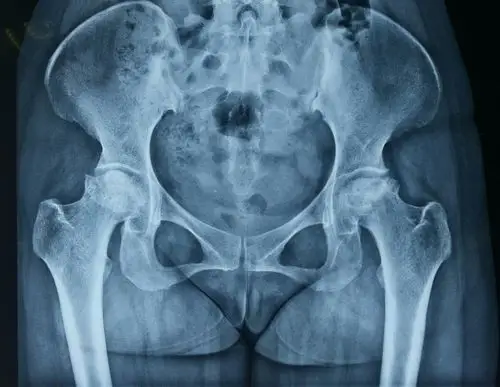

女性正常髋关节,骨盆和脊柱x线照片

x线检查 一般骨质无异常表现,有时可表现为骨盆轻度倾斜,髋关节囊肿胀